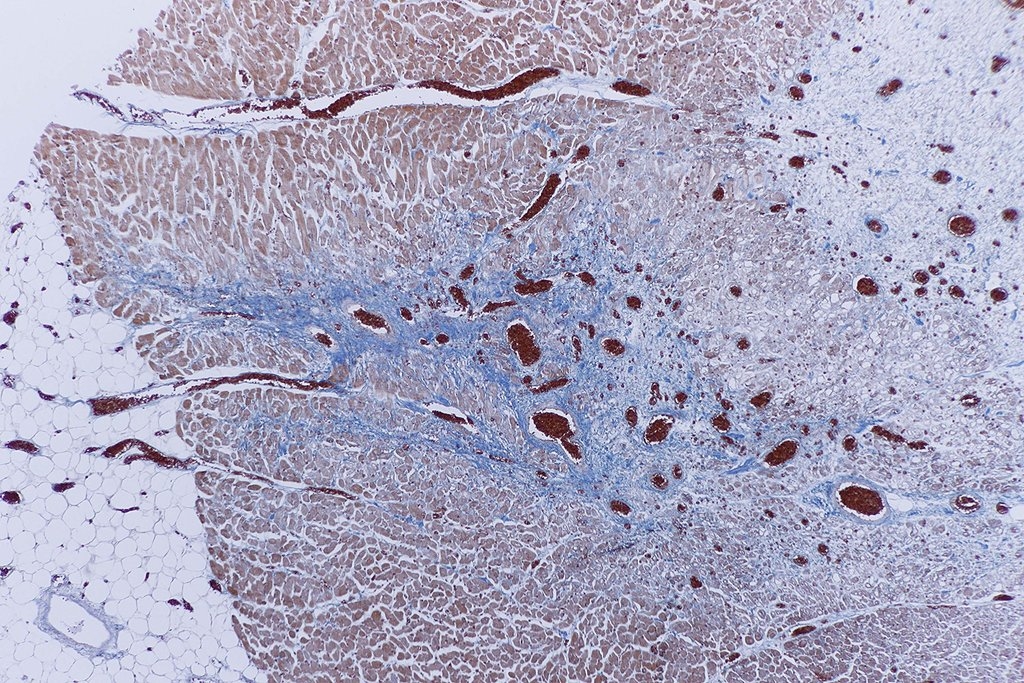

Bild 9 zeigt nun die entstandene Narbe im Paraffinschnitt,

blau in der Mallory-Färbung.